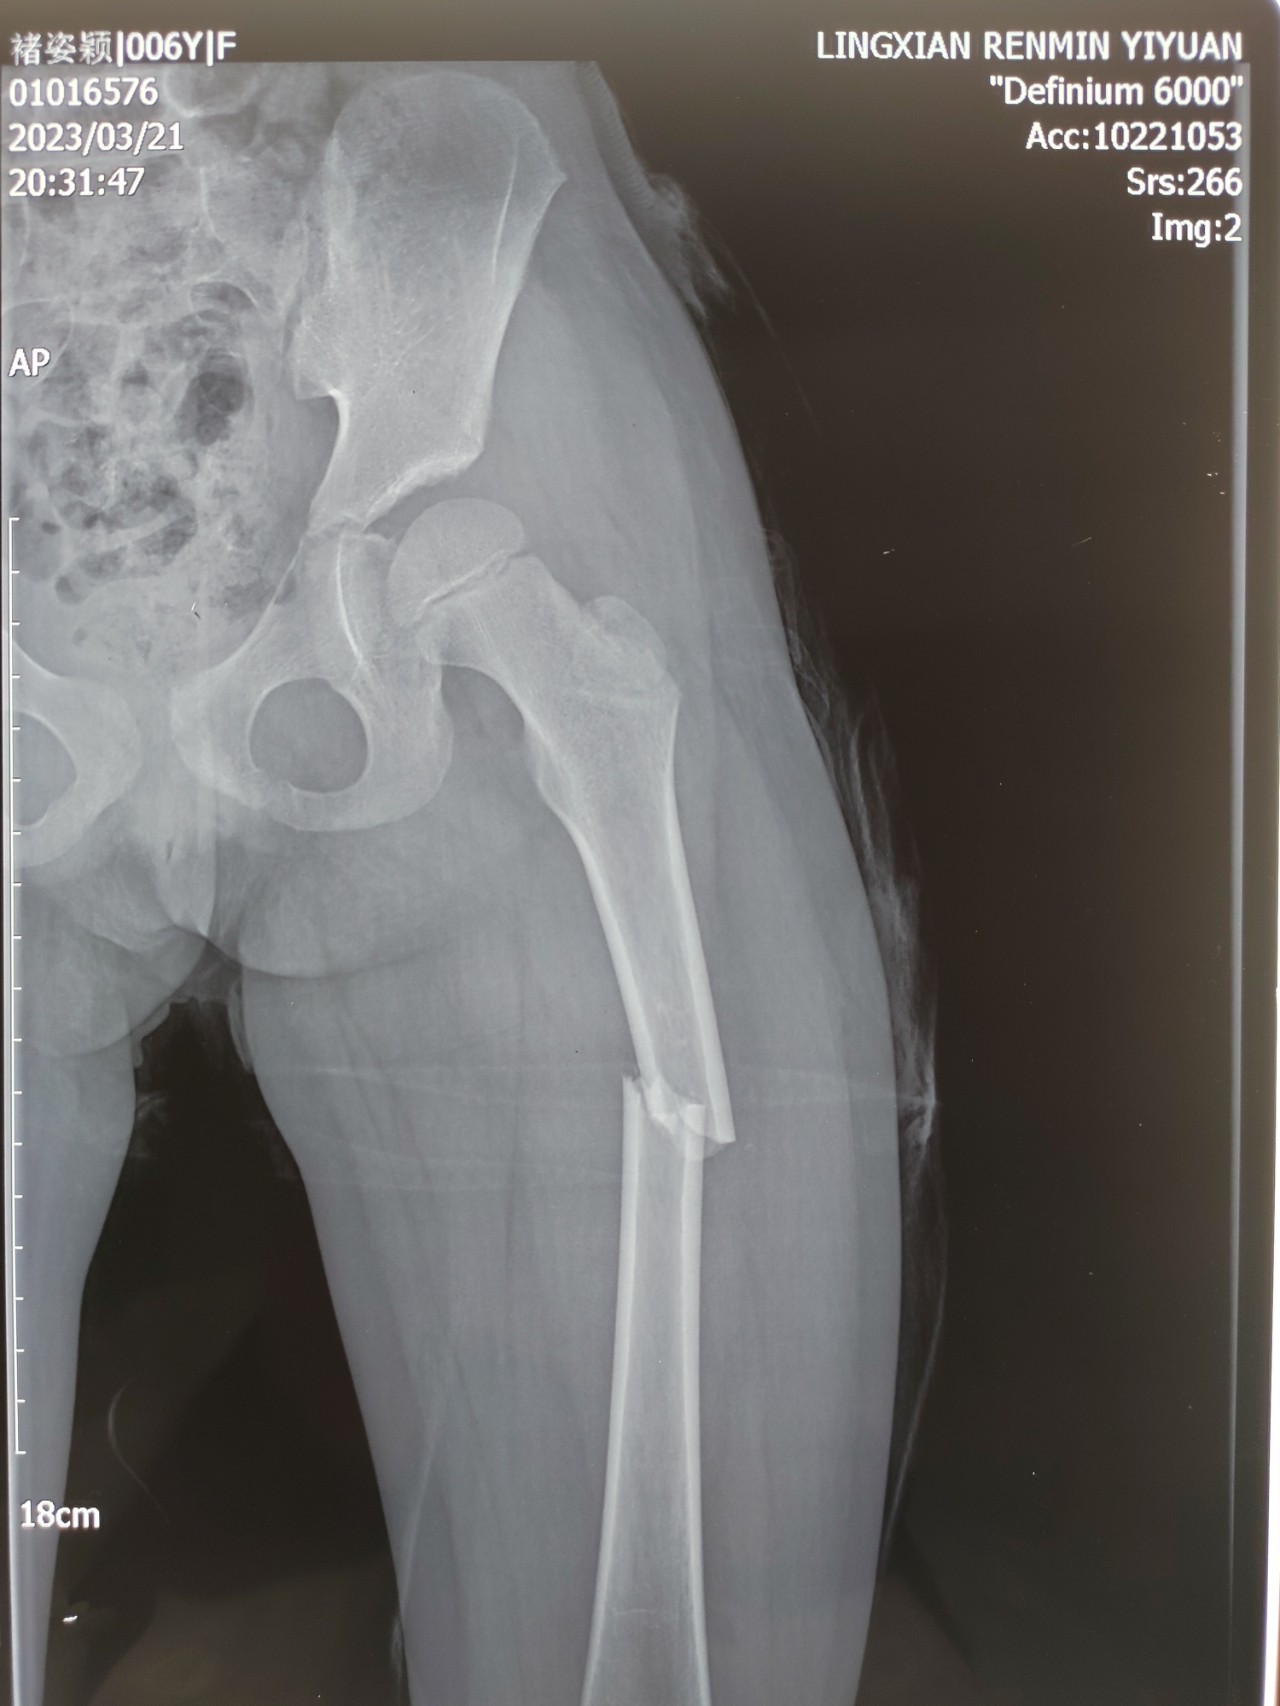

近日来,陵城区女孩李X卖袜救父的故事牵动着许多人的心,女孩父亲所确诊的鼻咽癌也因此进入大家的视线。作为我国高发的恶性肿瘤之一,鼻咽